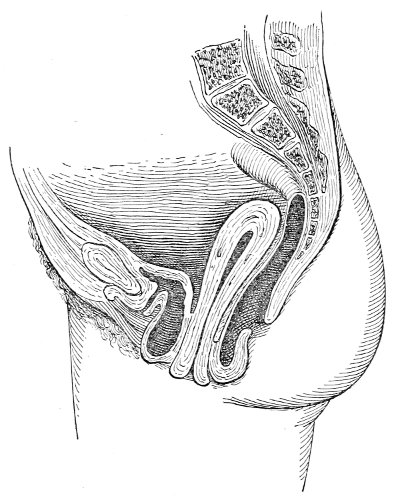

Fig. 3.—Bimanual examination; median sagittal section of the pelvis.

An accurate knowledge of the anatomy and mechanism of the female perineum is essential to an understanding of the nature and treatment of injuries to this structure. The anatomical structures lying between the anus behind and the symphysis pubis in front are those that most directly interest the gynecologist. Proceeding from 57 below upward, we find the following structures lying in superimposed planes: the skin, the superficial fascia, the deep layer of the superficial fascia, the transversus perinæi and the sphincter vaginæ muscles, the anterior layer of the triangular ligament, the posterior layer of the triangular ligament, the levator ani muscle (Fig. 19).

The vagina passes through these structures. They surround and support the ostium vaginæ as the fascia and muscles surround and support the opening of the rectum or the anus. The muscles and fasciæ are attached in the median line between the anus and the vagina, and therefore this part of the body, which is called the perineum, is supported or maintained in its 58 proper position by these various structures. The transversus perinæi arises from the ramus of the ischium and is inserted in the perineum. The bulbo-cavernosus, or sphincter vaginæ, arises in the perineum and is inserted in and about the clitoris. The inner fibers of the levator ani arise from the symphysis pubis and are inserted in the perineum and the lower part of the vagina (Fig. 20). When these muscles contract, their action, therefore, is to draw the perineum upward and forward. At the same time the anus is drawn upward and forward, and so also is the posterior margin of the ostium vaginæ and the lower portion of the posterior vaginal wall.

The vagina has no circular sphincter like the anus, but 59 the vaginal month is kept closed by the action of the transversus perinæi, sphincter vaginæ, and levator ani muscles, which draw the perineum forward, and thus keep the posterior vaginal wall in apposition with the anterior wall.

Fig. 22.—Sagittal section showing relations of the several layers of fascia within the pelvic floor (Dickinson).

The vagina extends, as a transverse slit in the pelvic floor, upward and backward, approximately in the direction 60 of a line drawn from the ostium vaginæ to the fifth sacral vertebra. It is approximately parallel with the conjugate of the brim, so that when the woman is erect the long axis of the vagina is inclined at an angle of 60° to the horizon. The vagina is not a vertical open tube: it is a slit in the pelvic floor, in health always closed by the accurate apposition of the anterior and posterior walls (Fig. 21). The anterior vaginal wall is about 2½ inches long in a vertical mesial line. The posterior vaginal wall is about 3½ inches long. The vaginal walls are triangular in shape, being broader above than below. The shape of the normal vagina at the pelvic outlet is shown by Fig. 23. The section here shows the vaginal 61 slit of the shape of the letter H. The portions of the slit extending backward and somewhat outward are called the vaginal sulci or furrows. They are directions of diminished resistance in which tears are liable to occur.